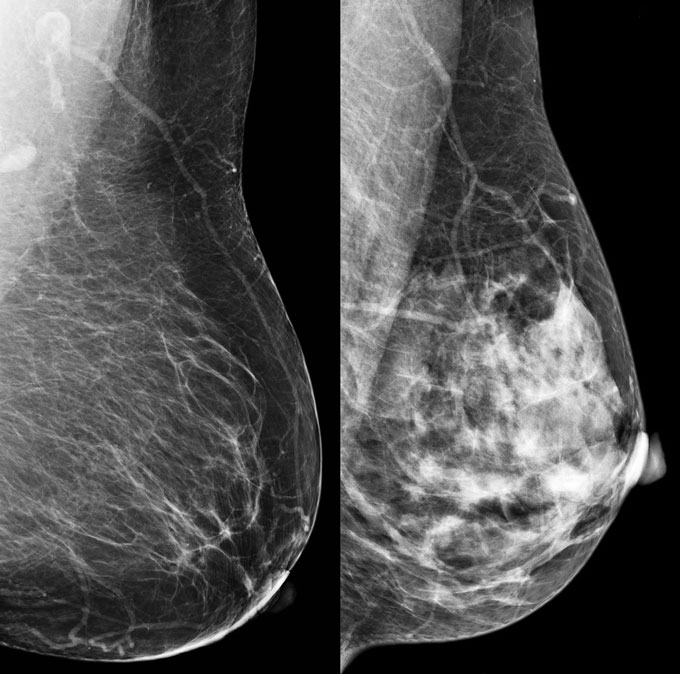

A new rule for mammograms

Mammography reports in the United States must now include whether the examined person has dense breast tissue, according to an FDA rule that went into effect September 10. Having dense breasts modestly increases the risk of a breast cancer diagnosis but is just one component of a person’s overall risk (SN: 3/10/23).